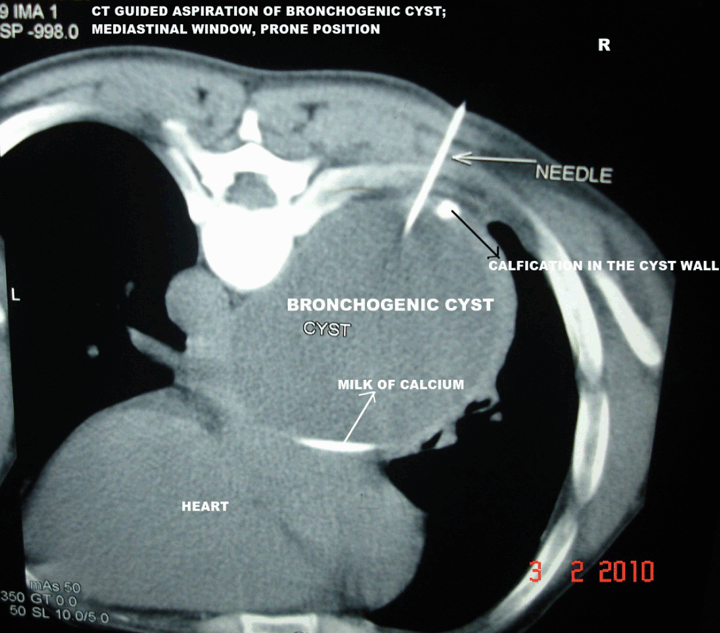

A 35-year-old male patient was presented with sense of heaviness in chest and shortness of breath even at rest for past two years. He gave history of intermittent low grade fever, cough, right sided pain chest since his adolescence and was frequently treated with antibiotics. Chest X-ray showed a right sided mediastinal mass with ipsilateral peripheral pleural calcification in the mid/lower zone. Electrogram and echocardiography were within normal limits. The CT scan of thorax showed a right sided posterior mediastinal, unilocular, cystic mass lesion having diameter of 10.9x8 cm with a homogeneous, increased fluid attenuation value of +15 HU. (Figure 1) On contrast study the cyst was thin-walled, nonenhancing except a small part of its right edge suggesting focal thickening of inflamed mediastinal pleura or compressed part of lung adjacent to the cyst. (Figure 2) A fluid was found at its dependent part, both in supine and in prone position due to presence of a small amount of higher density fluid. (Figure 1) (Figure 2) and (Figure 3) A focus of calcification was found in a part its periphery. (Figure 3) Absence of air within the cyst proved that the cyst was noncommunicating. Right intermediate bronchus was partially compressed and slightly displaced by the mass. (Figure 4) Associated ipsilateral periopheral pleural calcification was present. The CT guided aspiration revealed its content to be whitish, opalescent fluid with high protein, epithelial cells, amorphous calcium. Culture report was negative. Fibreoptic bronchoscopy revealed mucosal thickening and mild narrowing of lumen of right intermediate bronchus due to extrinsic compression. Bronchoscopic biopsy specimen revealed inflammatory changes and no malignant cell was detected.

Figure 3: Computed tomography scan guided aspiration of bronchogenic cyst; needle in situ, mediastinal window, prone position.